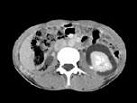

- 多项选择题女,32岁, 左腰部胀痛不适1年余,10年前因右输尿管结石、右肾重度积水行右肾切除术, CT检查如图所示,下列说法正确的是 ( )

A、平扫左肾周可见不规则的环形低密度影

B、增强扫描,肾皮质明显强化而周围的低密度影无强化

C、增强扫描肾实质期,肾实质强化而周围的低密度影无强化

D、增强扫描延迟期,肾实质强化减退而其周围则呈高密度影,对比明显

E、考虑为左侧尿外渗